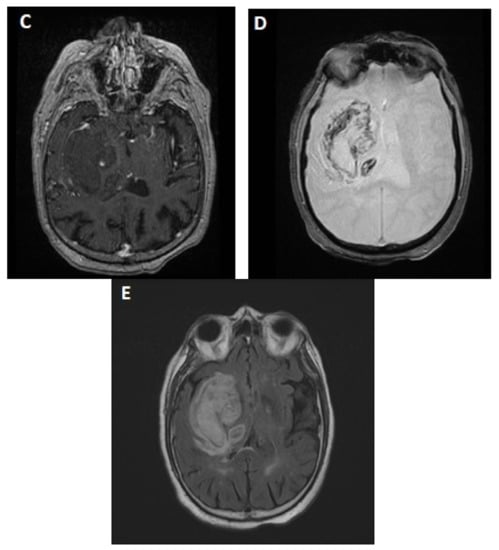

| Tumor | Lobar ICH; disproportionate edema; Mass effect | MRI showing mass lesion |